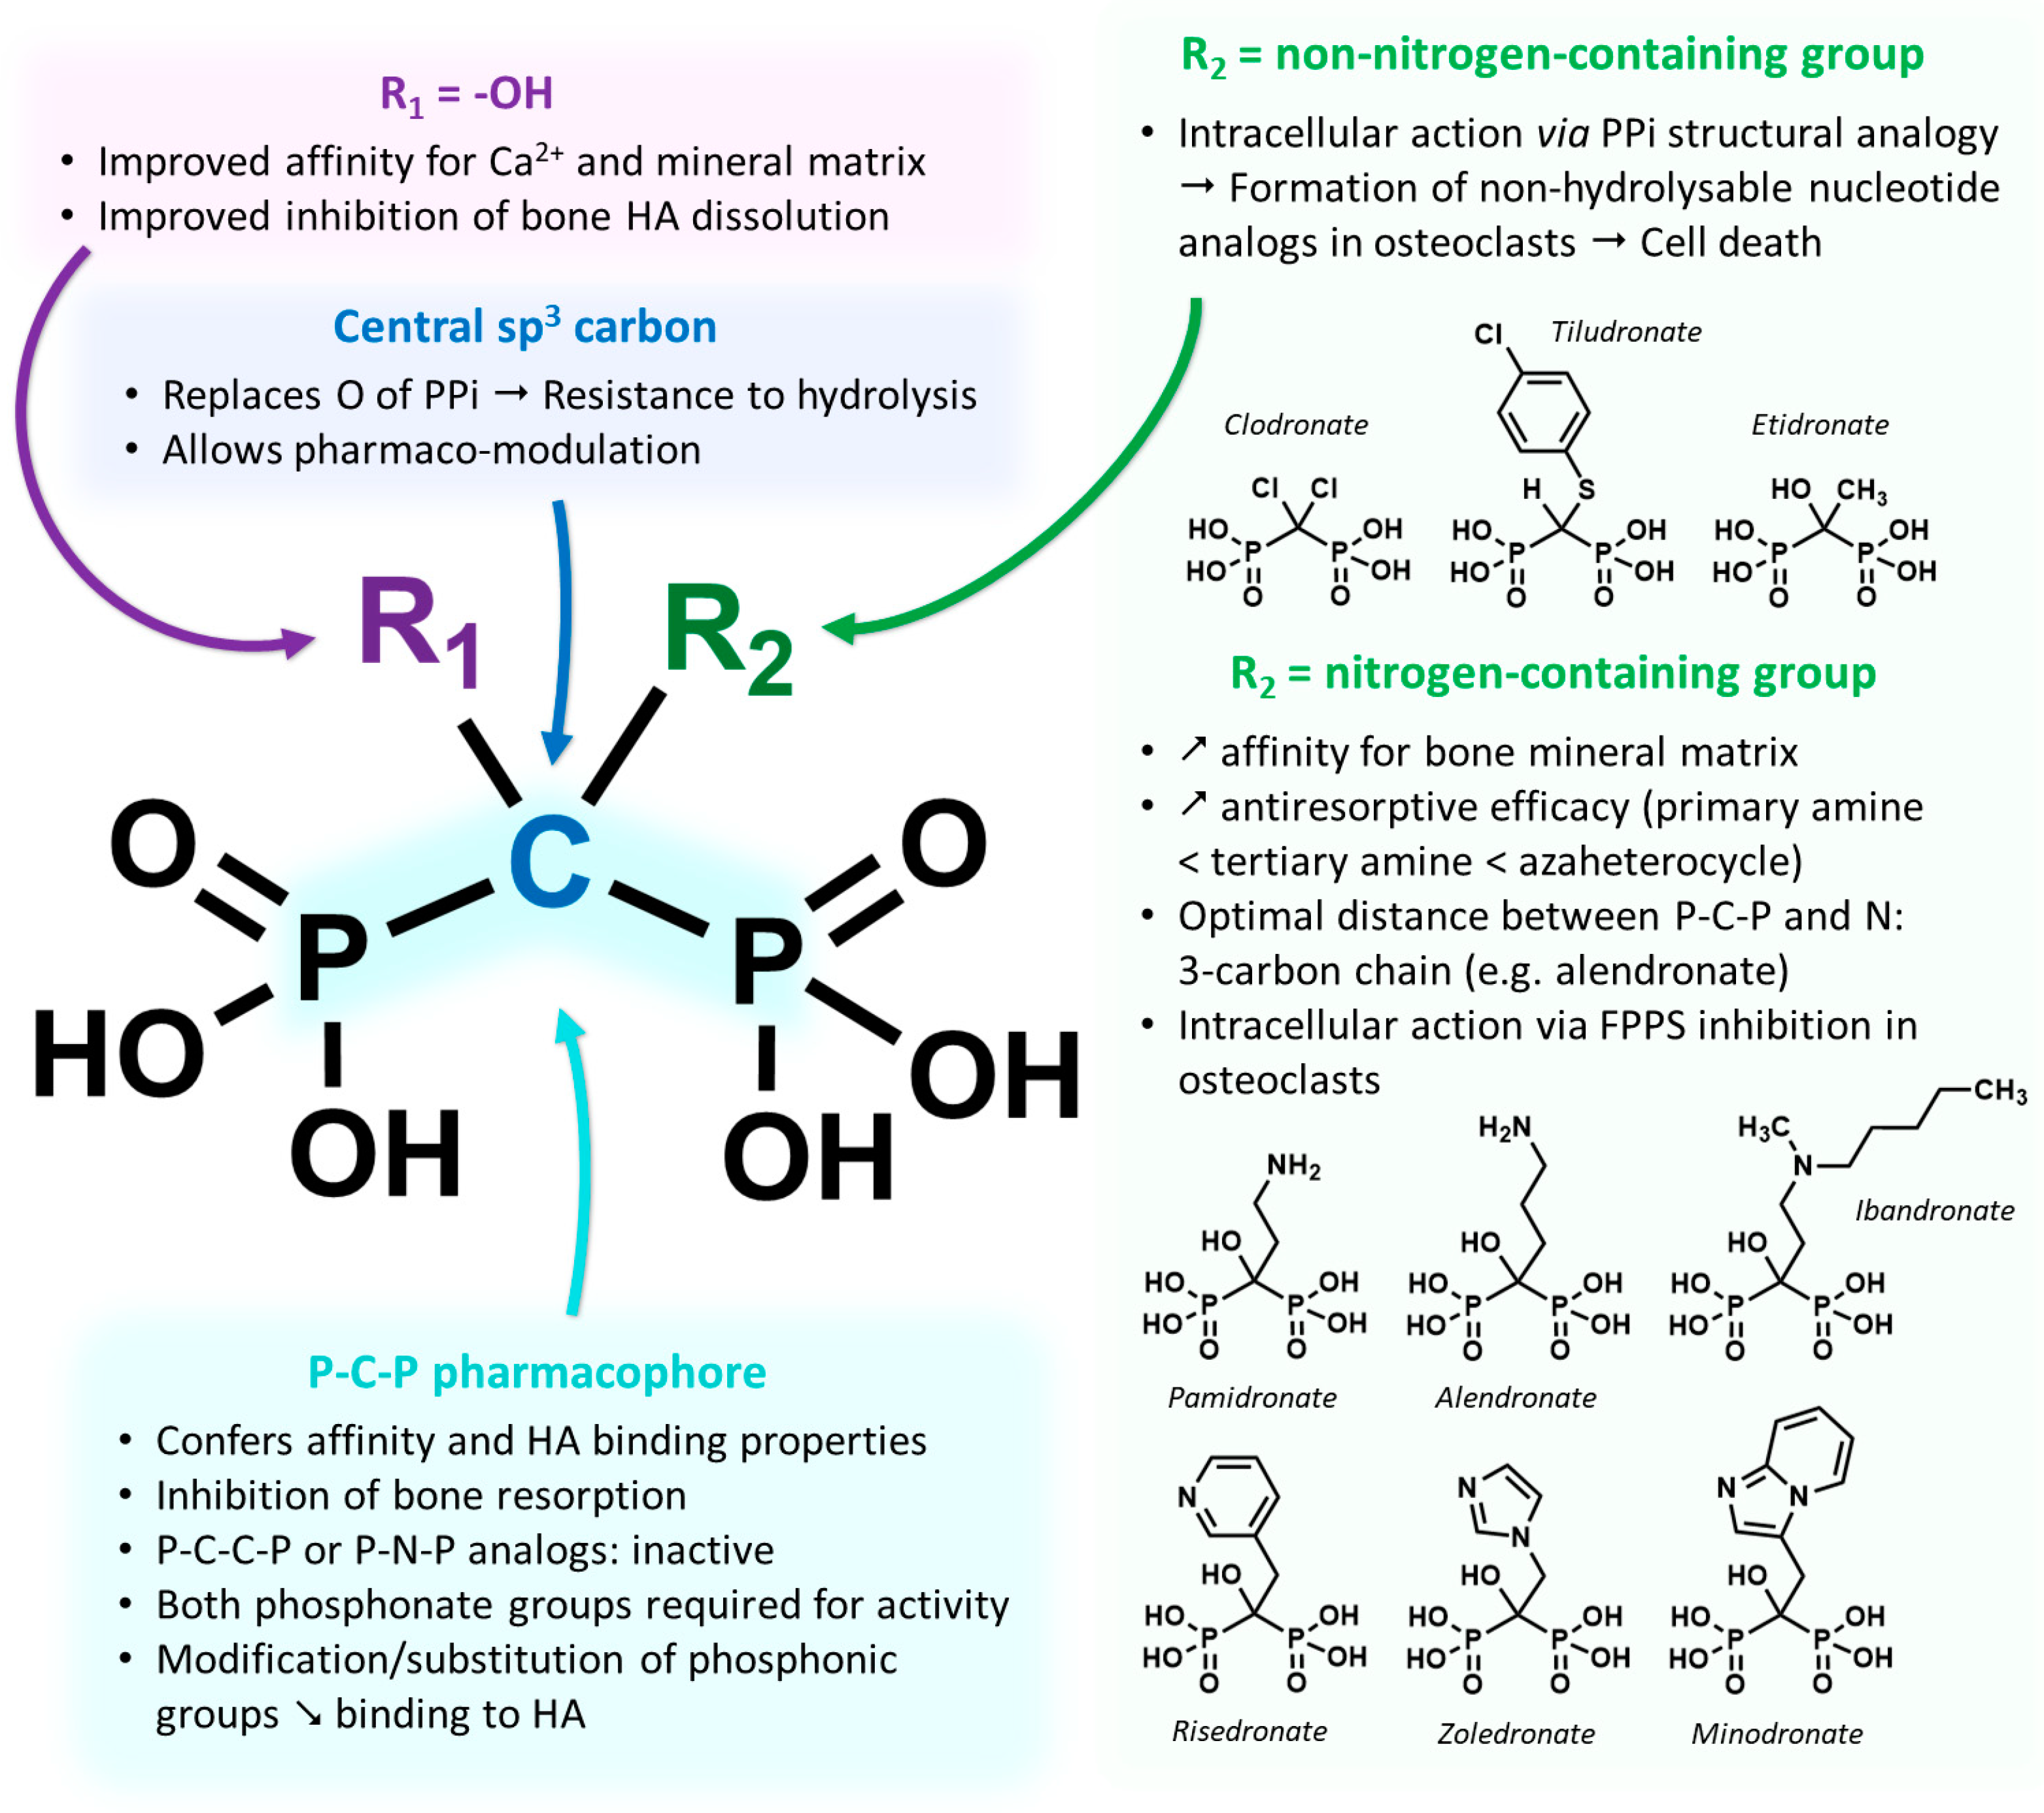

2.1. Development and Pharmacology Basics of Bisphosphonates

2.2. Bone Metastases Molecular Targeting and Early Bisphosphonate-Based Radiopharmaceuticals